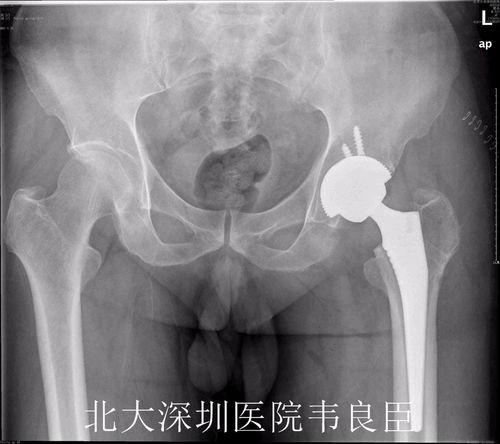

在完成股骨头置换后,医生会继续进行髋臼置换。首先,医生会在髋臼处切开一个小口,然后取出坏死的髋臼部分。接着,医生会植入一个新的髋臼,这个髋臼通常由陶瓷或金属制成。

视频中,我们可以看到医生正在为患者植入新的髋臼。手术过程中,医生需要确保新髋臼与股骨头紧密贴合,以恢复髋关节的正常功能。